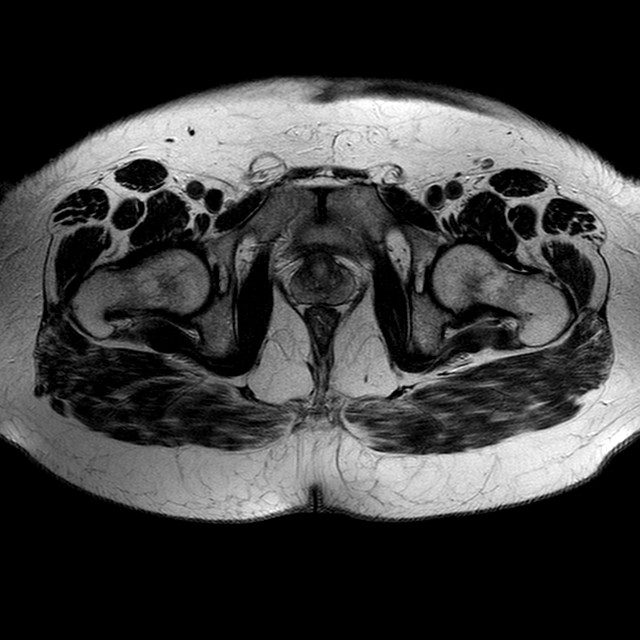

Esami: RMN BACINO

T2w TSE

Evidenti e simmetriche alterazioni osteofitosiche in regione coxo femorale con riduzione delle rime articolari. Degenerazione completa del cercine glenoideo. Non attuali segni di versamento articolare. Non segni di edema osseo che escludono attuale algodistrofia od osteonecrosi. Lieve e simmetrica riduzione del trofismo della muscolatura glutea.